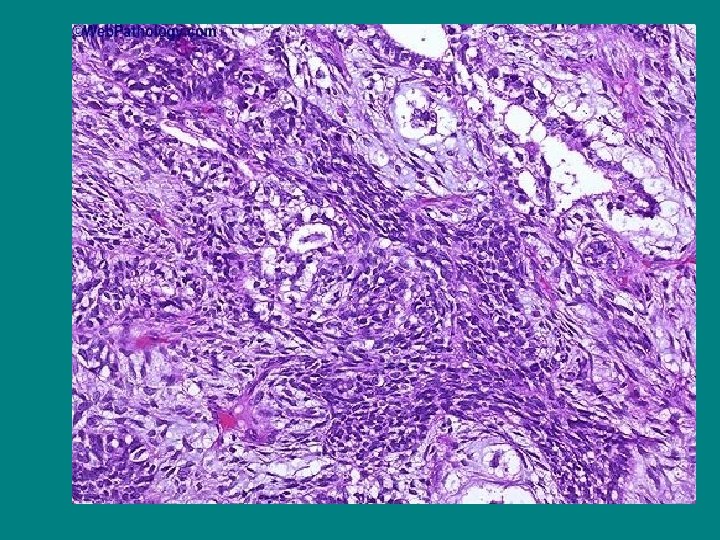

SEMINOM • Solid, homogen, utan cystor eller större nekroser • Välavgränsad, men kan vara multifokal • Både strål- och cytostatikakänslig • Kan metastasera som annan typ av groddcellstumör